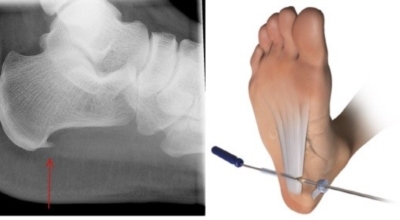

비수술적 치료로 대부분 족저 근막염 증상이 완화될 수도 있지만 일부 환자는 수술이 필요한 경우가 있어요. 수개월간의 비수술적 치료를 했음에도 발 통증이 계속되면 수술을 고려해봐야 하며 수술을 통해 족저 근막을 증가시키는 방법을 고려해 볼 수 있다고 해요.

최근 관절경을 이용해 족저 근막 절개술을 시도하기도 하는데 수술적 치료의 성공률은 70~90%로 높게 알려져 있어요. 하지만 수술 후 신경 훼손 등과 같은 합병증이 유발될 수 있기 때문에 잘 알아보고 전문의와 상담후 수술을 결정하시는게 좋답니다.

비수술적 치료 방법에으로 보조기, 체외쇼크파, 스트레칭, 스테로이드 주사요법, 비스테로이드성 소염진통제 등이 여러 방법들이 있어요. 족저근막염 발생초기에는 스트레칭을해서 족저근막 및 아킬레스건을 효과적으로 증가시키는 것만으로 추가적인 피해를 예방할 수 있답니다. 또한 보조기를 착용하여 뒤꿈치에 가해지는 쇼크을 완화 시킬 수 있답니다. 발에 부기가 발생된 경우 진통주사를 이용해 치료할 수 있어요. 수술적 치료로 들어가기 전 체외쇼크파를 이용해 증상완화의 효과를 볼 수 있다고 하죠.